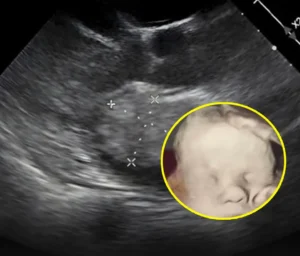

Una madre de Kentucky, Amanda Foster, compartió una ecografía de su bebé en la que parece verse una mano gigante sosteniendo la cabeza del feto. La imagen se volvió viral, transmitiendo esperanza y consuelo, especialmente tras su difícil historial de embarazos, incluyendo la pérdida de su primer hijo por una condición médica.

Amanda relató que su hijo Jay nació sano, y ahora espera otro bebé con una condición cardíaca congénita. Para ella, la ecografía fue un símbolo de protección y cuidado en medio de la incertidumbre médica.